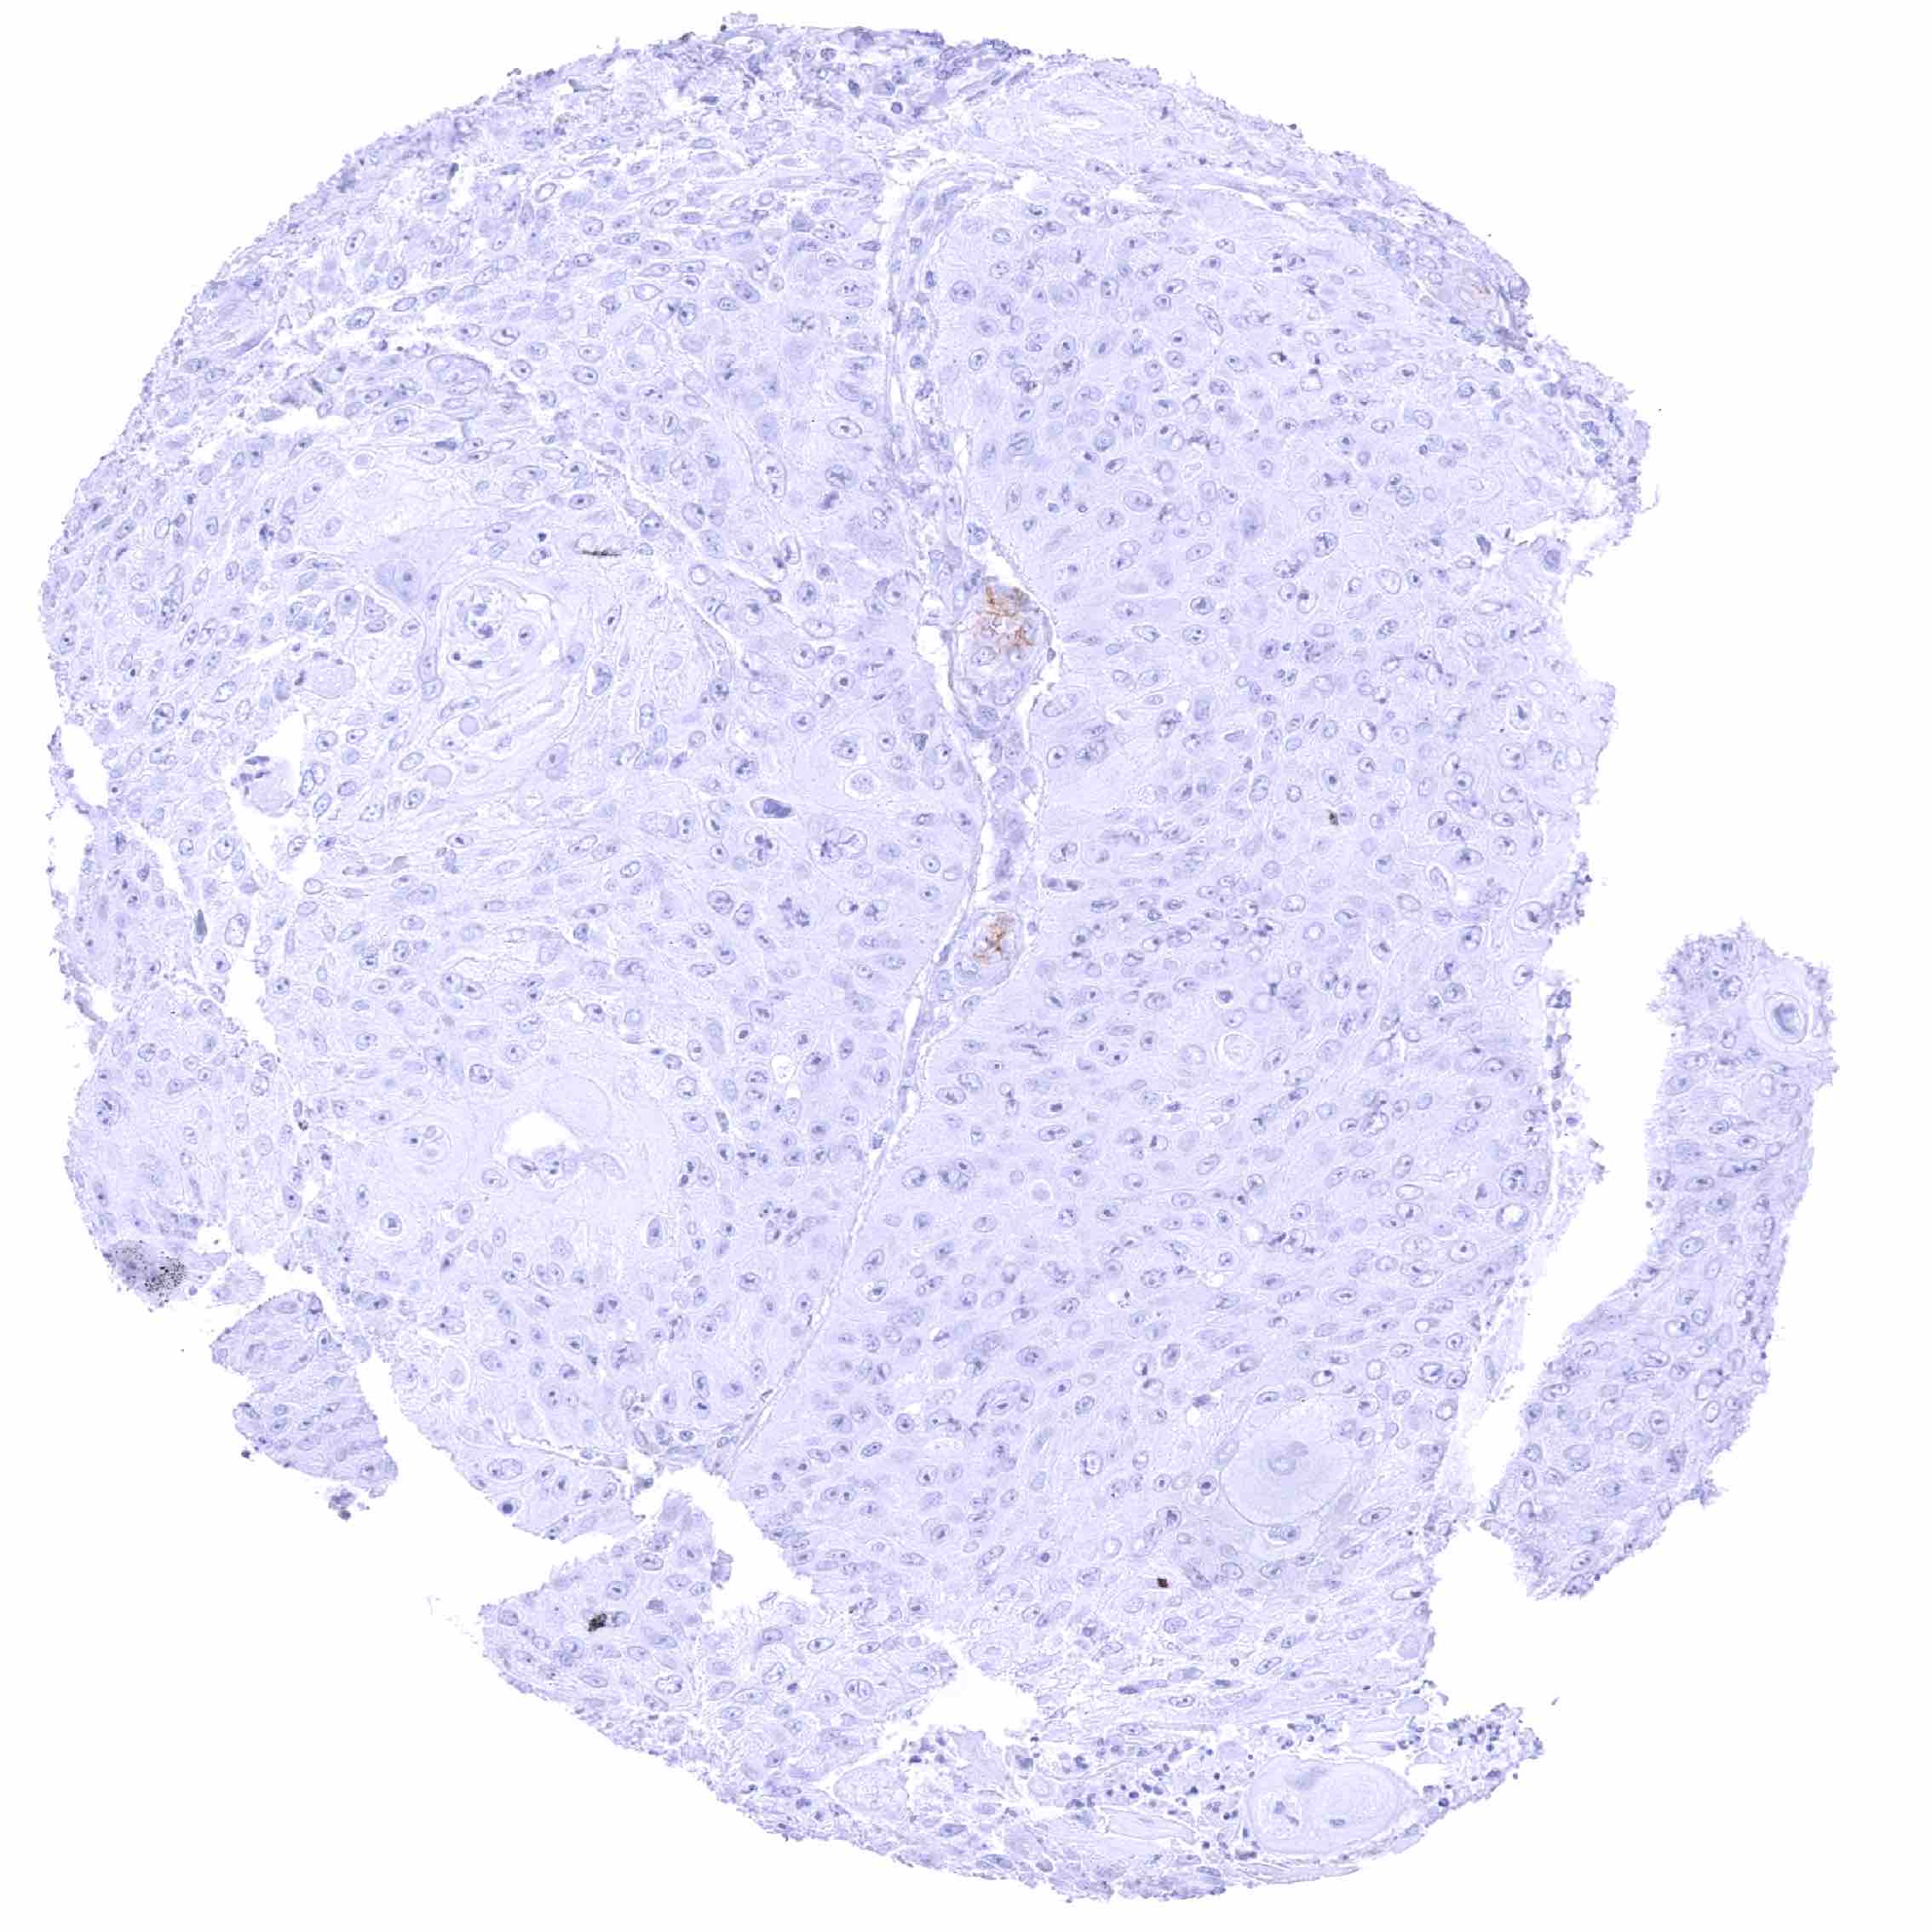

Breast – PODXL negative invasive breast cancer of no special type (NST). .jpeg